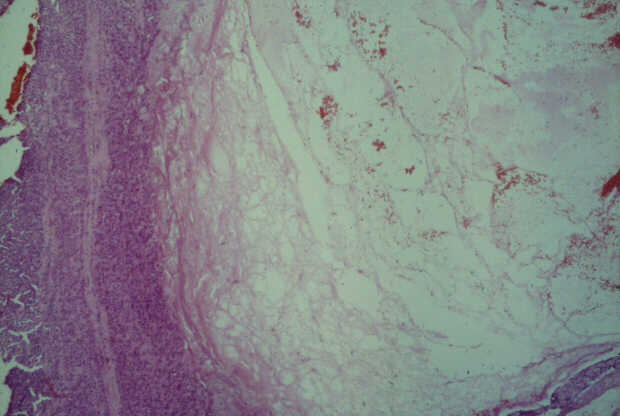

Balazs Járay1, Eszter Székely1, Tamas

Winternitz2, Zsolt Tarján3,

Tibor F. Tihanyi2

12nd

Department of Pathology, 21st Department of Surgery, 3Department

of Radiology, Semmelweis University. Budapest, Hungary